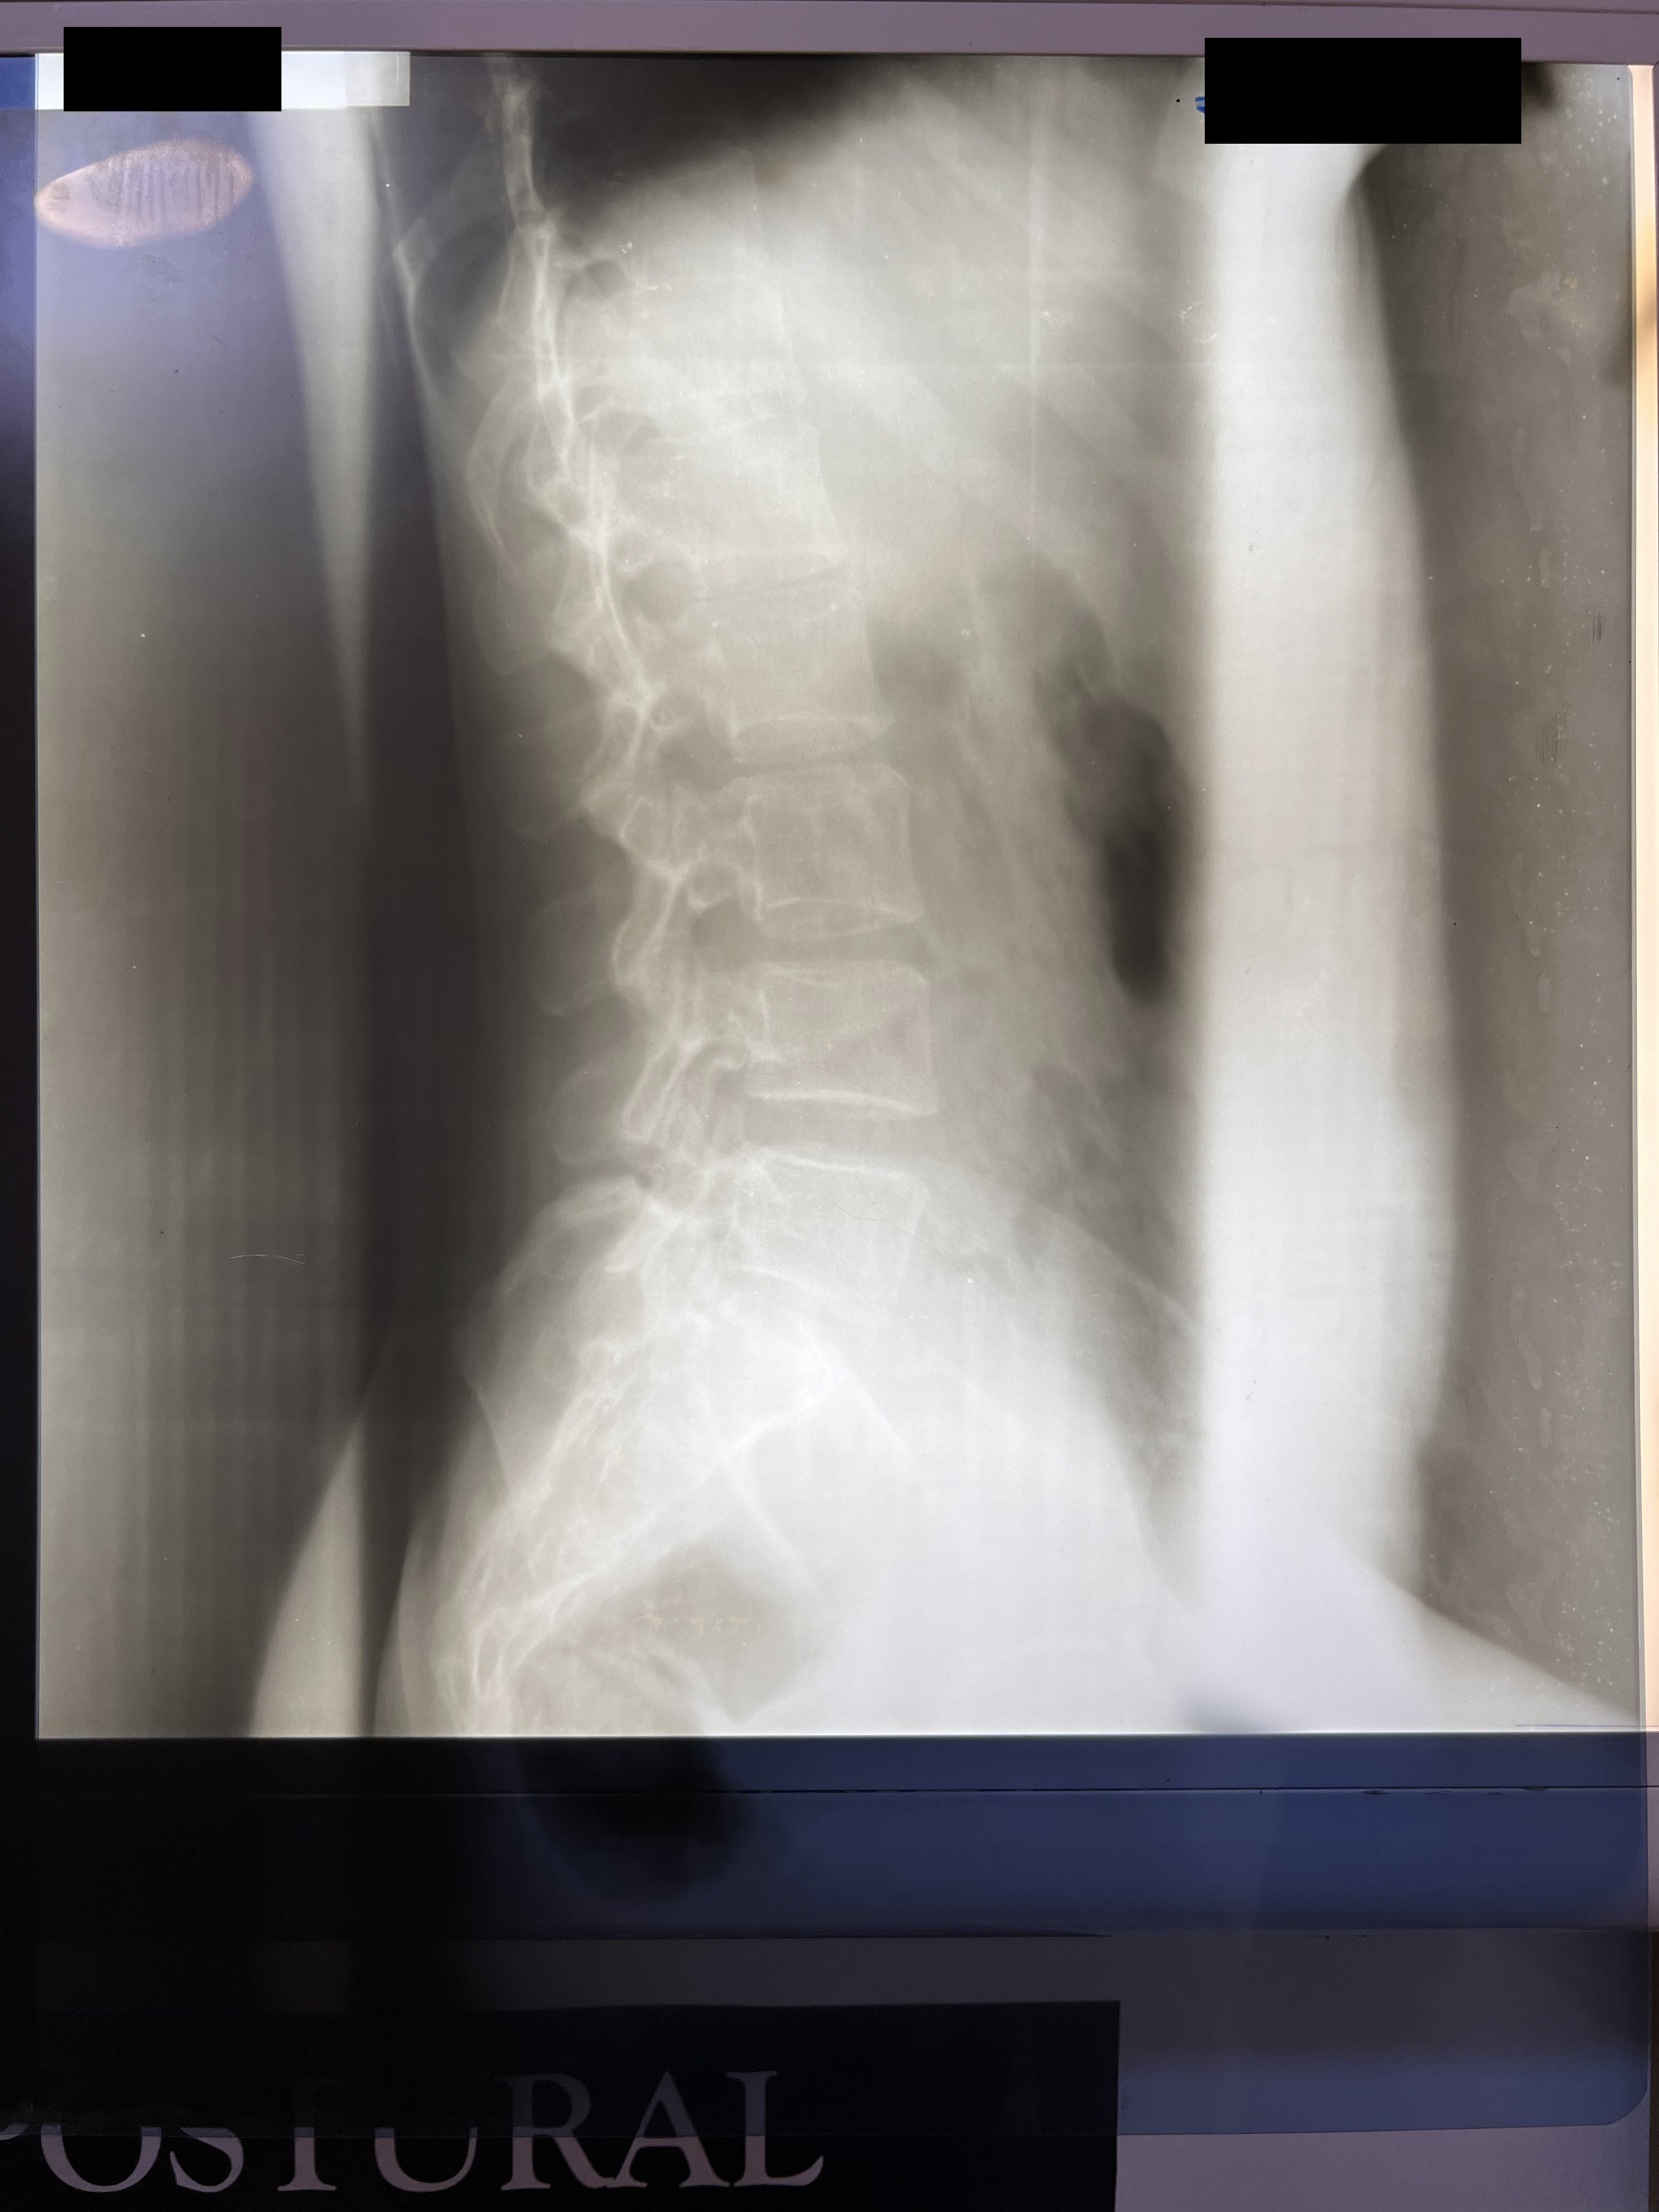

Chiropractic X-Rays

In partnership with Nova Wellness Centre led by Dr Asheley Ashietey in Accra, we conducted chiropractic examinations of 100 women working as kayayei in Kantamanto Market ranging in ages from 15 to 44, with varied experience carrying in the market from those who had been working for a few weeks to some women who had carried bales for 20 years. Nearly every study participant reported significant pain as a result of headcarrying and x-rays indicated spinal deterioration and deformities beginning within months on the job. Such physiological impacts coupled with severely polluted, cramped and violent living conditions set the stage for catastrophic injury.